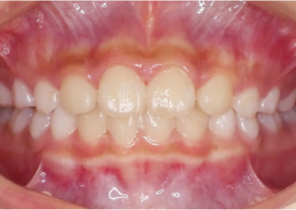

Case Report 1

10 years 0 months old, 18 stages of Invisalign Palatal Expanders

Courtesy of Dr. Sandra Khong Tai

Pre Invisalign Palatal Expander Expansion

Post Invisalign Palatal Expander Expansion

After Invisalign First treatment